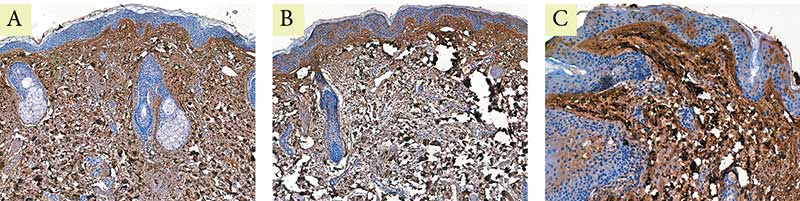

Рис. 6. Пациентка Л. Экспрессия маркера эластина: A –  до процедуры; B – через месяц после процедуры; C – через пять месяцев после процедуры